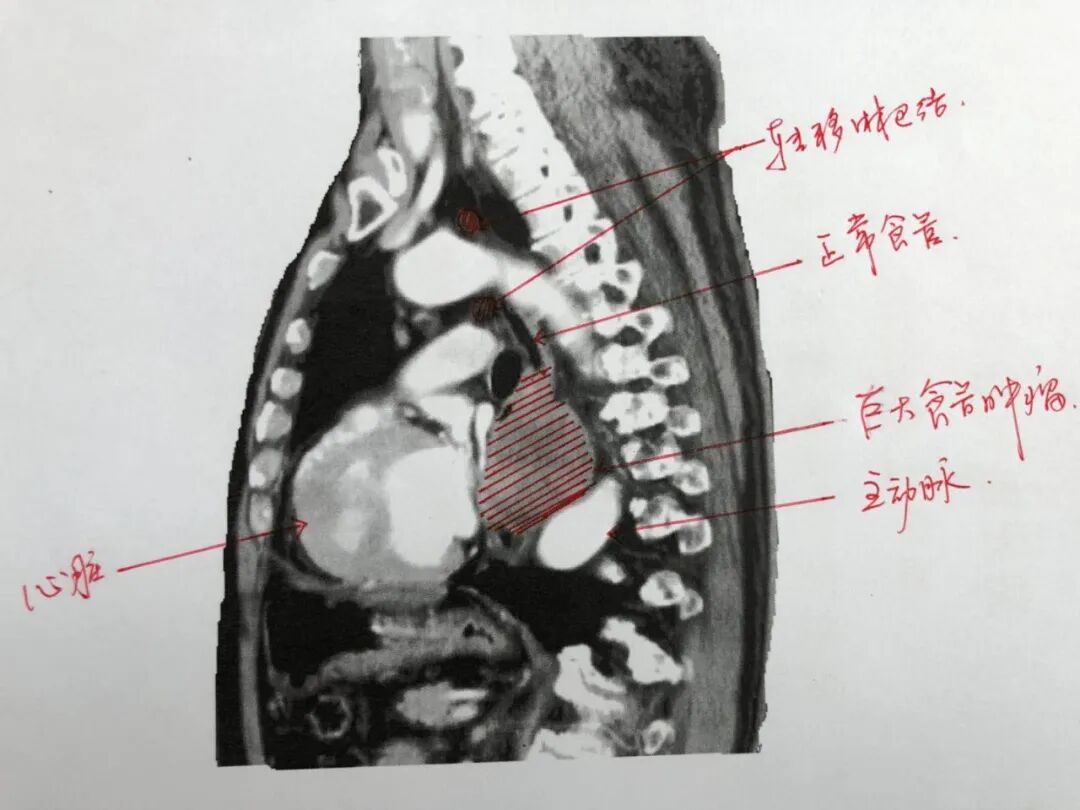

76岁的陈大爷退休十多年了,一直身体硬朗很少生病,连感冒都很少有,更是很少去医院。最近,突然出现了不明原因的呕吐,在医院体检发现患了食道肿瘤。来江苏省肿瘤医院就诊时,从事肿瘤胸外科工作20多年的蒋峰主任也感到吃惊。食管是空腔器官,管腔只有大拇指粗细,肿瘤大多向内生长,直径通常小于2CM。而陈大爷的肿瘤是向外生长,环绕着食管浸润周围的器官,纵膈完全被占满,但是食管内的侵犯并不多,食管肿瘤外向生长到拳头大小,直径有食管的5倍。

病人和家属急切地想知道还有没有手术的机会。蒋峰主任说,食管癌首选手术。但这个这么大的食管肿瘤实属罕见,手术困难要比常规手术大得多。一是容易引发大出血。肿瘤体积太大,左侧心房被挤压变形,周围有主动脉、肺动脉等大血管。在剥离肿瘤时损伤任何一个血管都会引起大出血,抢救成功机率极低;二是肿瘤完全剥离困难。肿瘤已经有10*8CM,形状不规则,占满了整个纵膈,右侧出现多个肿大淋巴结。既要保护好心脏和大血管,又要完整剥离肿瘤清扫淋巴结,又不损伤心脏和血管,难度极大。

尽管术前做了充分的评估和准备。手术时,仍然让他们感受到巨大的压力,实际情况更加复杂。不规则的肿瘤已经占满整个纵膈,与正常组织不仅界限不清,还广泛粘连,给剥离肿瘤带来了很大难度。为了彻底清扫右侧淋巴结,医生选择了右侧开胸,手术视野明显受到了影响。剥离左侧的肿瘤时,手术助手用手托起肿瘤,俞明锋主任完全凭着丰富的“手感”保护血管,一点点地剔除肿瘤。随后又小心翼翼地切除了一部分心包。经过四个小时的紧张手术,团队完整地剥离了肿瘤,切下来的肿瘤有10*8CM,是手术团队遇到最大的食管肿瘤;右侧多个淋巴结也清扫干净,单个淋巴结有2CM大小。